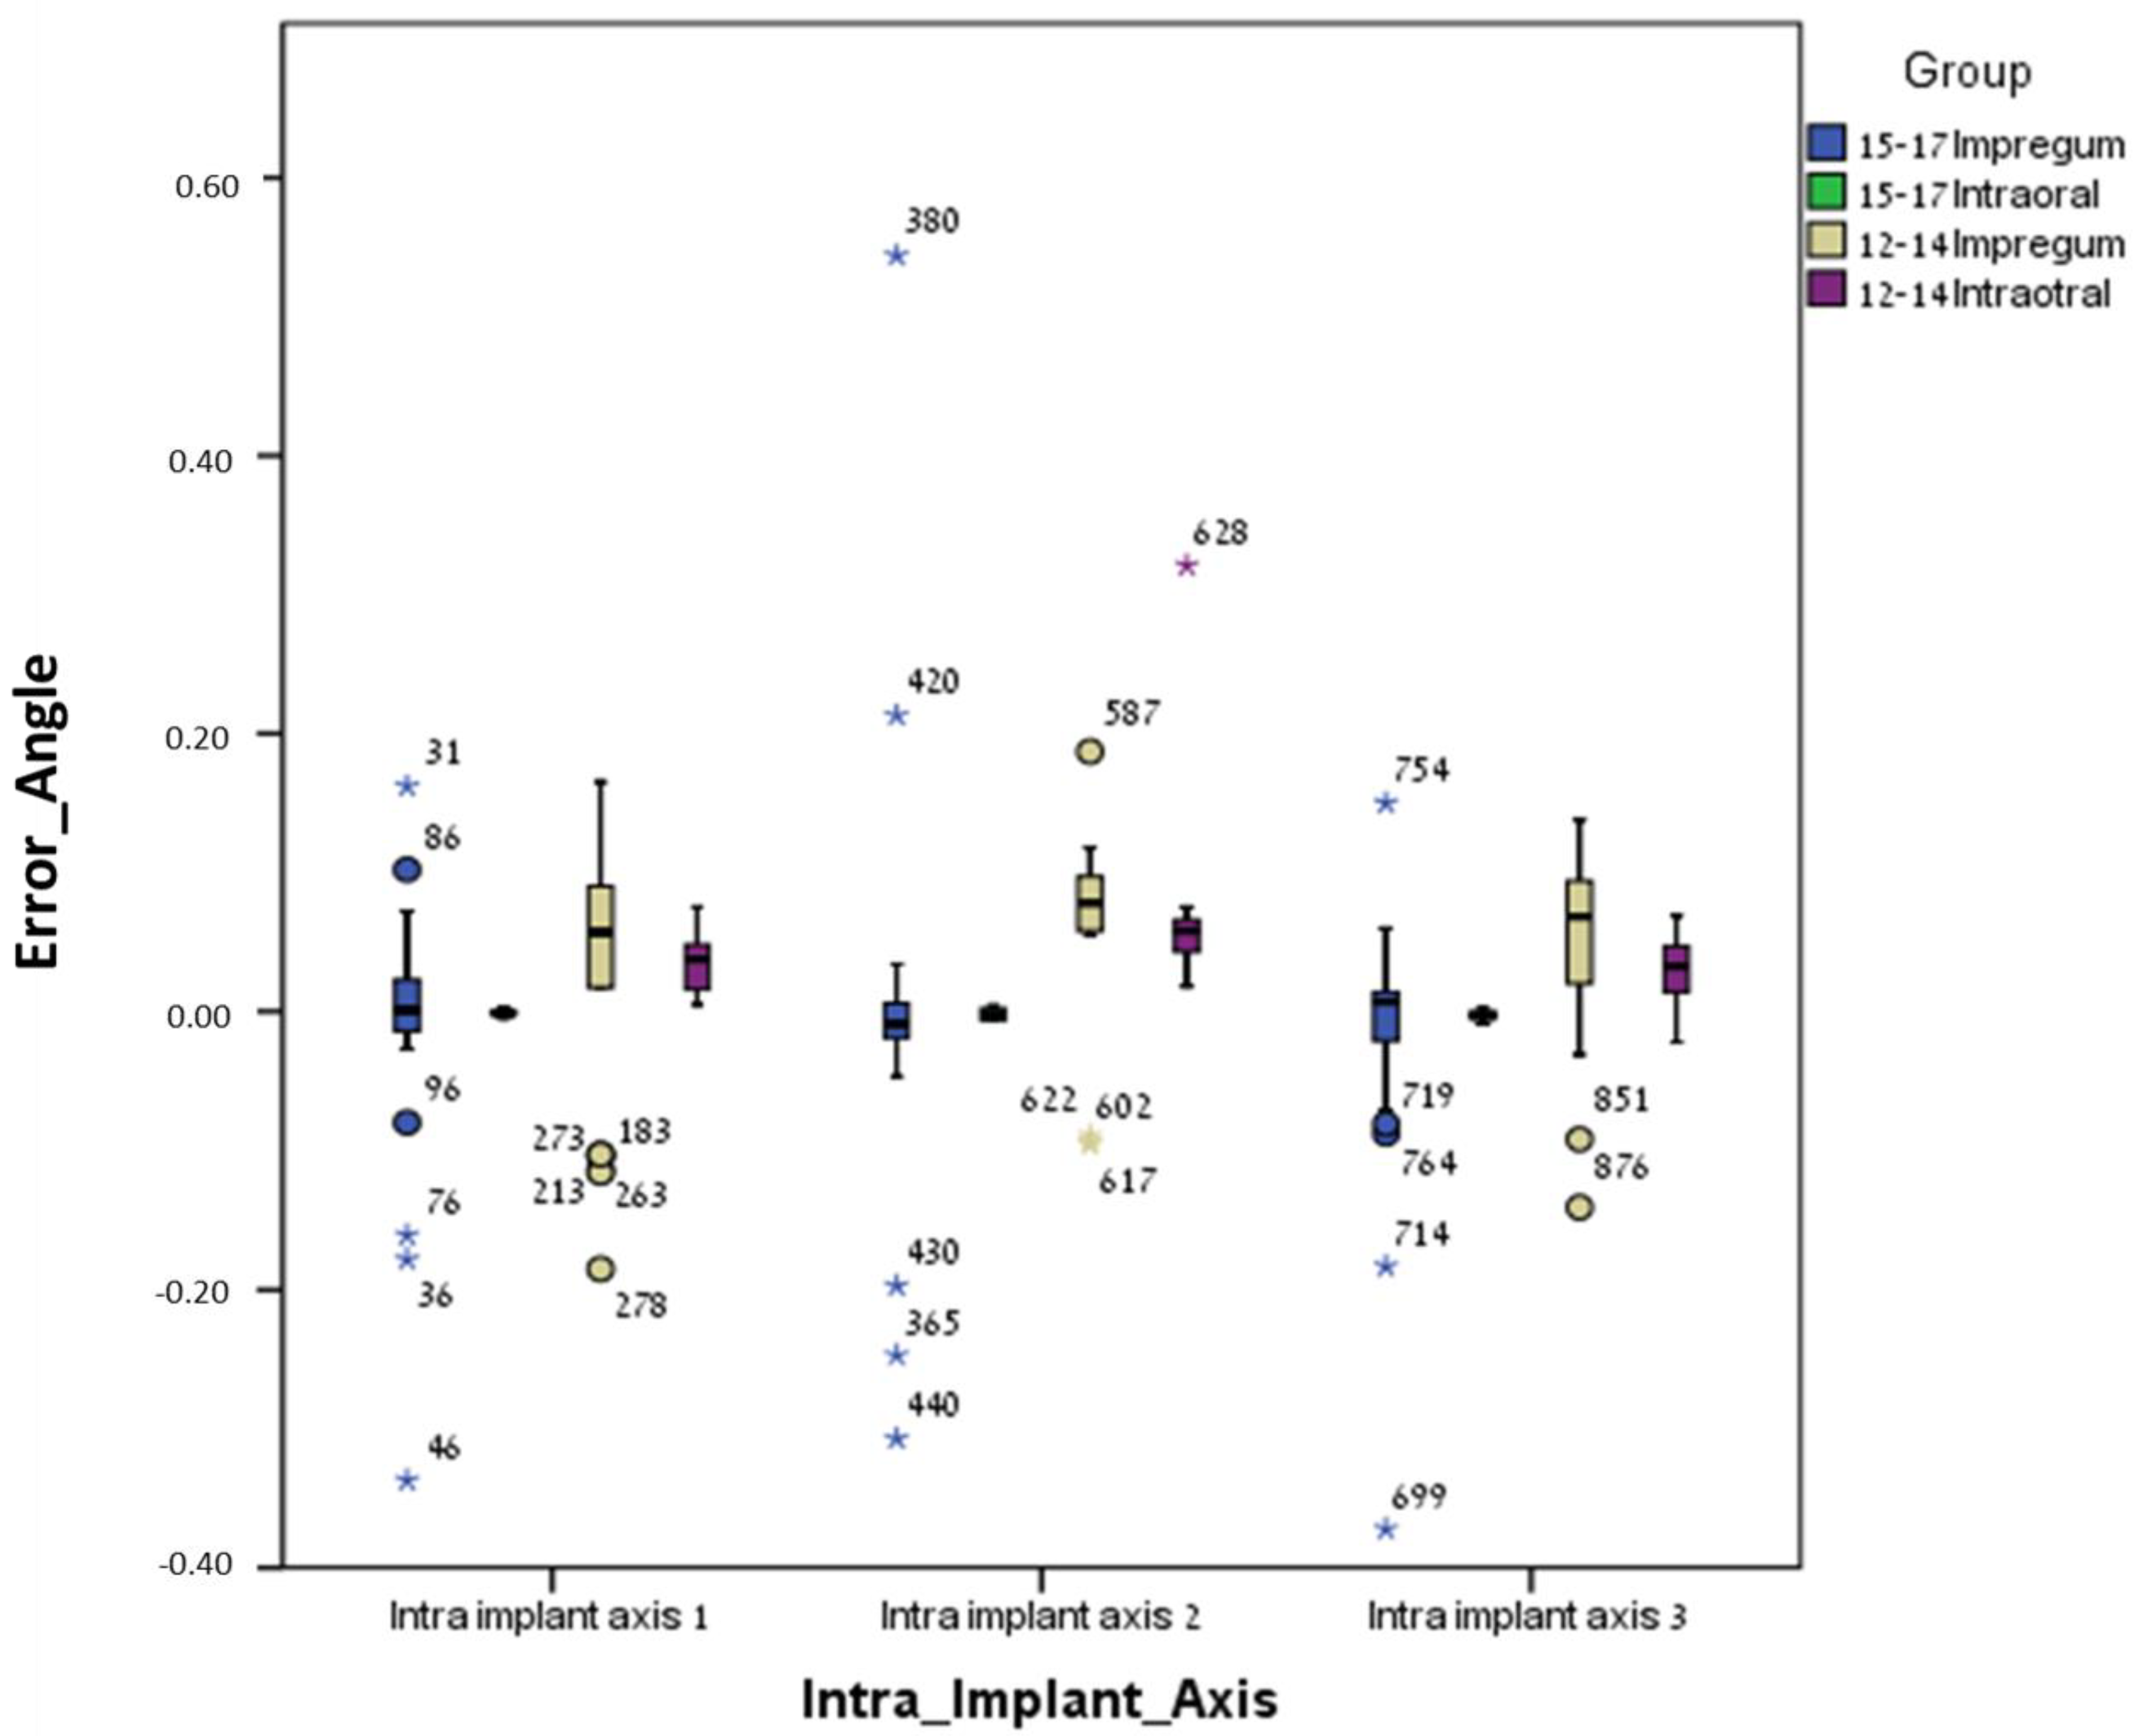

3. Results

3.1. Between Groups

3.2. Within Groups